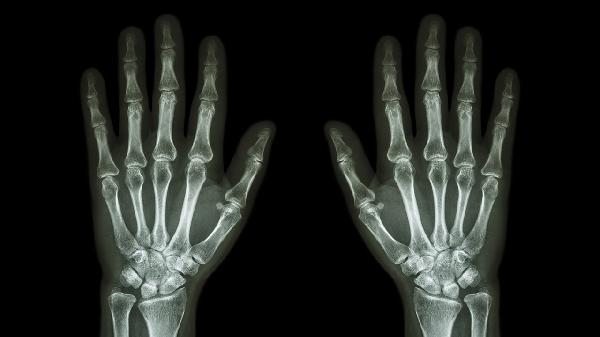

长期劳损或年龄增长可能导致拇指关节软骨退化,引发骨关节炎。症状包括晨起关节僵硬、活动时有摩擦感,后期可能出现关节变形。医生可能建议使用硫酸氨基葡萄糖胶囊、双醋瑞因胶囊等软骨保护剂,配合关节功能锻炼延缓病情进展。

自身免疫异常可能引发对称性关节肿痛,早期多累及近端指间关节和掌指关节,伴随晨僵超过1小时。需通过类风湿因子和抗CCP抗体检测确诊,常用甲氨蝶呤片、艾拉莫德片等抗风湿药物控制病情,生物制剂如阿达木单抗注射液适用于重症患者。